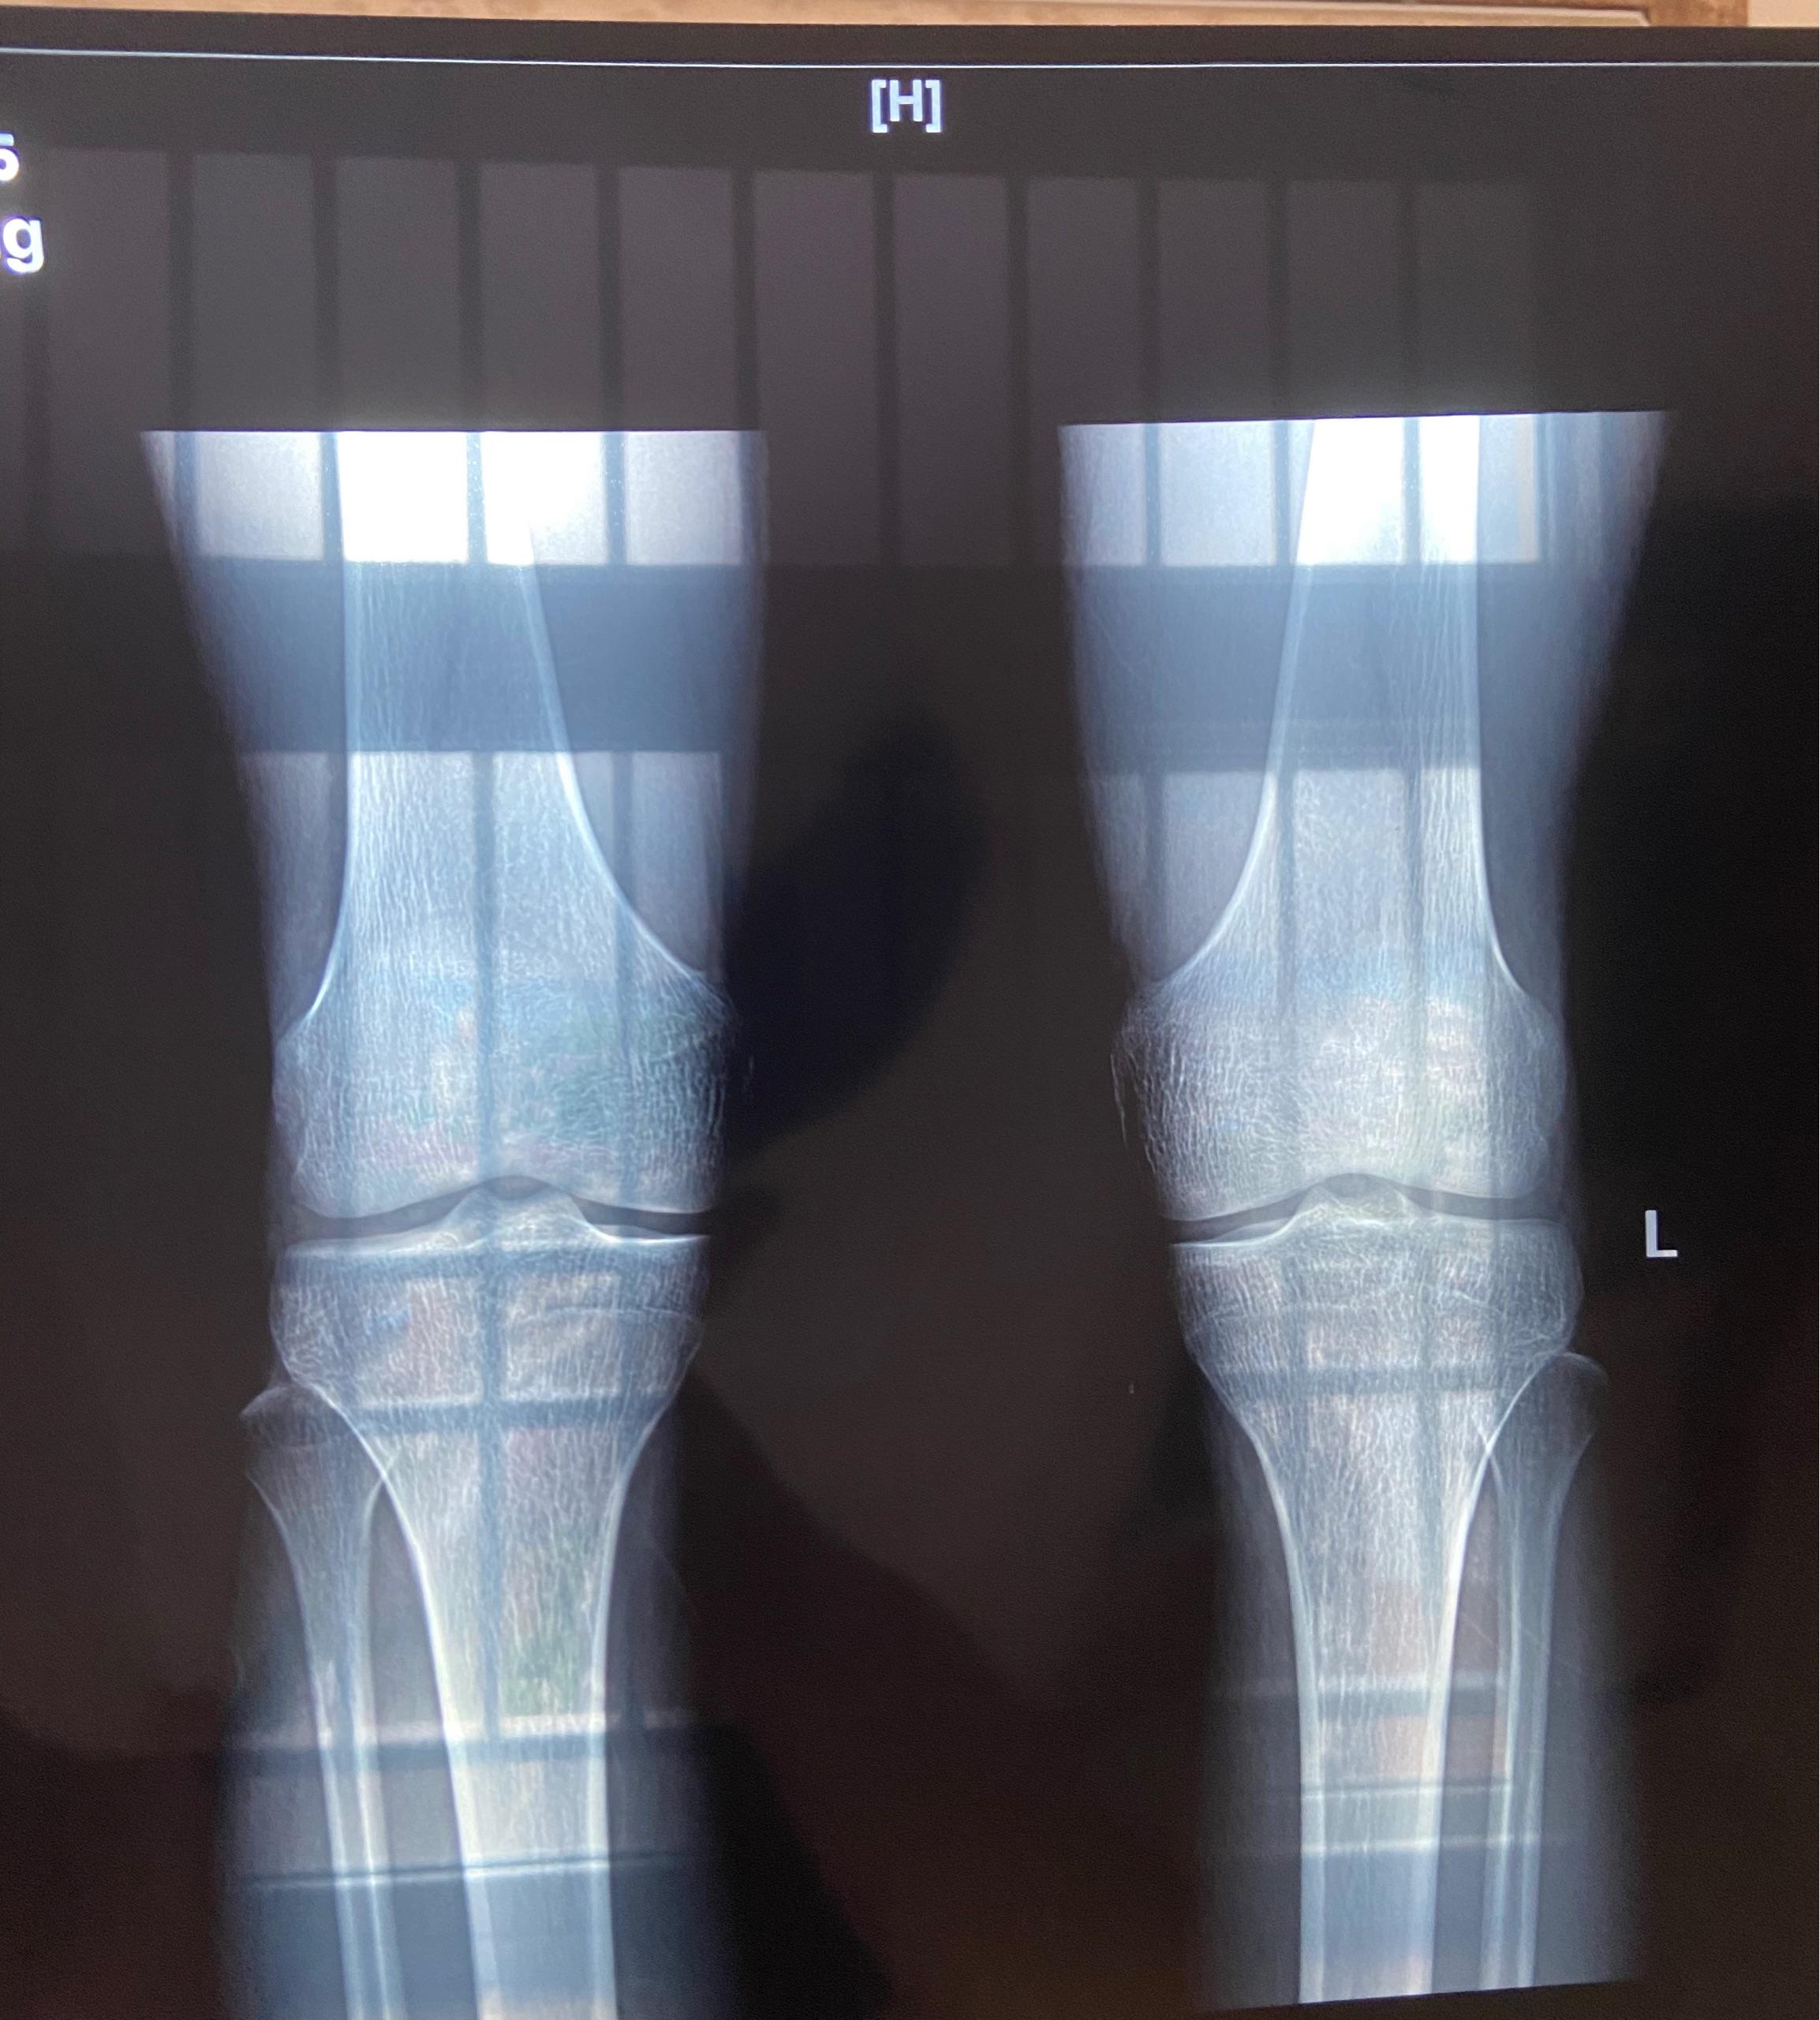

20.6.14兄弟萌,你们帮我康康我这片子算是什么。